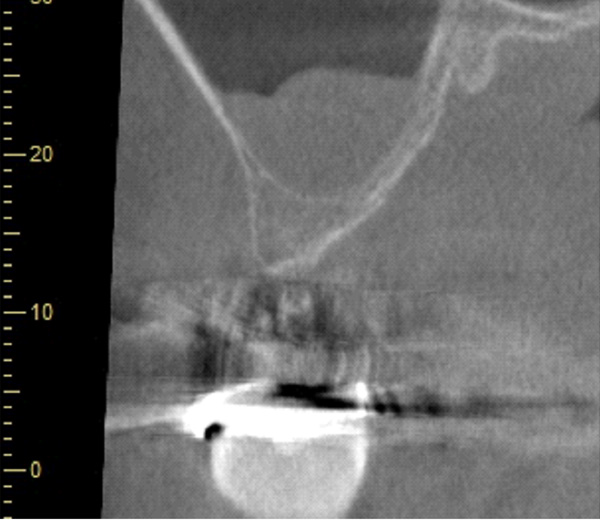

| 年代・性別 | 50代 女性 |

|---|---|

| 主訴 | 左上のブリッジがグラグラして外れそう |

| 治療期間 | 約18ヶ月 |

| 費用 | 1,600,000円 |

| 治療内容 | インプラント、骨造成、サイナスリフト、セラミック修復 |

| 治療に伴うリスク | インプラント周囲炎 セラミックの破折、脱離 |